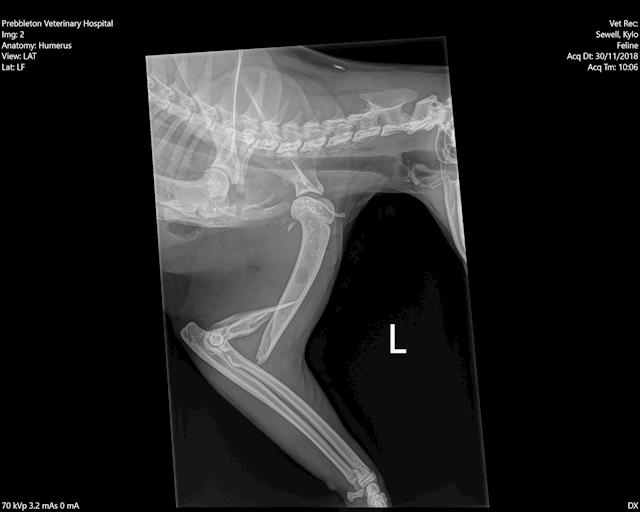

I have attached the X-ray that show the terrible fracture in Kylos humerus. The vet, Nick Page of Rolleston Vet services, has done an amazing job at trying to save Kylos leg.